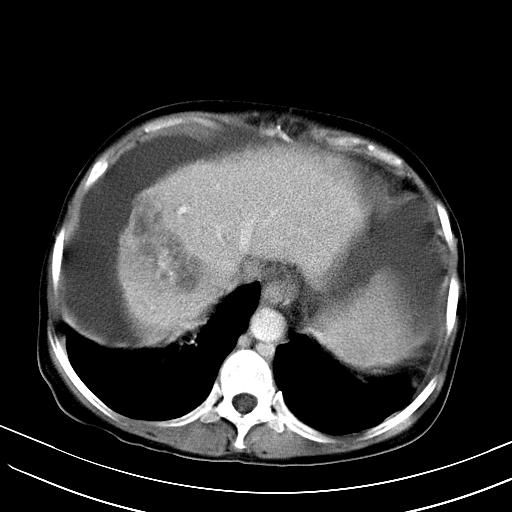

标题: CT23697:肝癌并肝动静脉漏? [打印本页]

标题: CT23697:肝癌并肝动静脉漏?

肝动静脉漏,动脉期肝动脉及门静脉内均可见造影剂……

1)肝右叶肝癌并肝动静脉漏。2)肝硬化,腹水。3)胆囊炎。

肝右叶肝癌并动静脉漏,肝硬化,腹水。

1)肝右叶肝癌并肝动静脉漏 门v右支瘤栓伴海绵样变。2)肝硬化,脾大 腹水。3)胆囊炎。门v高压.

右叶肝癌并肝动静脉漏(动脉期肝动脉及门静脉内均可见造影剂),肝硬化,腹水。(胆囊壁水肿)

1)肝右叶肝癌,考虑并发肝动静脉漏。扫描时间好像慢了。2)肝硬化,门脉高压、脾大、腹水。